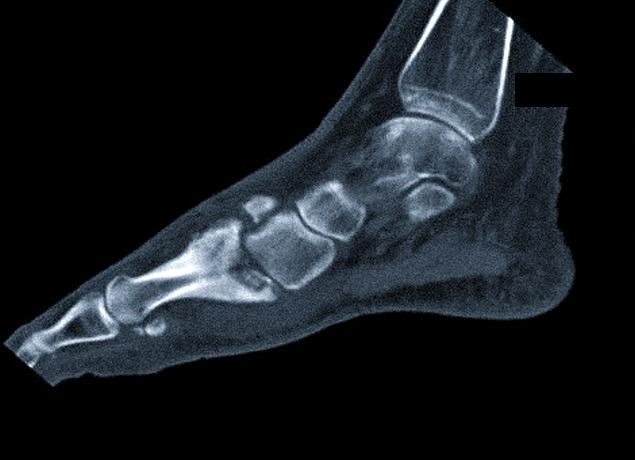

Компьютерной томографией (КТ) стопы называется послойное изображение костных и хрящевых структур дистального отдела нижней конечности.

Компьютерная томография стопы позволяет получить детализированный снимок структуры нижней конечности

КТ стопы позволяет получить при помощи рентгеновских лучей послойное изображение данной области и создать в итоге модель в трёхмерной визуализации. Получаемые в итоге снимки отображают следующие органы:

• фаланги пальцев;

• плюсны;

• предплюсны;

• голеностопные суставы;

• нижние отделы костей голени.

КТ – это метод послойного трехмерного отображения структуры органа. При проведении КТ стопы рентгеновский сканер перемещается, посылая один за другим снимки на монитор компьютера:

1. В любом «срезе» стопы четко видны мягкие и костные ткани, их конфигурация и объем.

2. Малейшая киста, опухоль или изменение контуров отражаются на серии снимков, которые позволяют точно определить локализацию патологии.

3. При деформации кости сразу понятно, за счет какой структуры (губчатого вещества или кортикальной пластинки) она произошла. Компьютерная томография выявляет точную причину деформации кости

4. Туберкулезную деструкцию костей стоп можно определить только с помощью КТ.